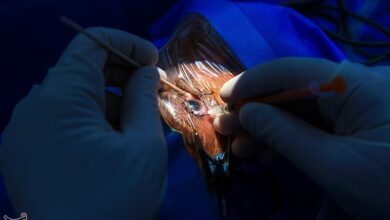

خطر پارگی چشم و نابینایی بر اثر استفاده از مواد منفجره

قاسم فخرائی در مصاحبه ای با خبرنگار اجتماعی آژانس اجتماعی تاسنیم گفت: هر سال چهارشنبه شب شاهد وقایع بد هستیم…